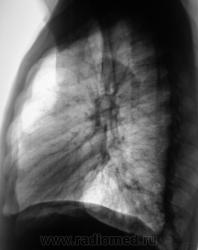

А куда будем "девать" правую верхушку?

Как по мне - пара мелких плотных теней...как то остальное - "не глядится"...или как Вы говорите - "глаз не цепляется"...может немного с поворотом лежал, потому и вуалеподобное затемнение, может техногенного характера....

Так значит - экзацербация опухолевой тканью "старых" очагов (очаги уплотнения в круглой тени)?

Похоже что так. А архива нет, за сколько выросло это "чудо"?